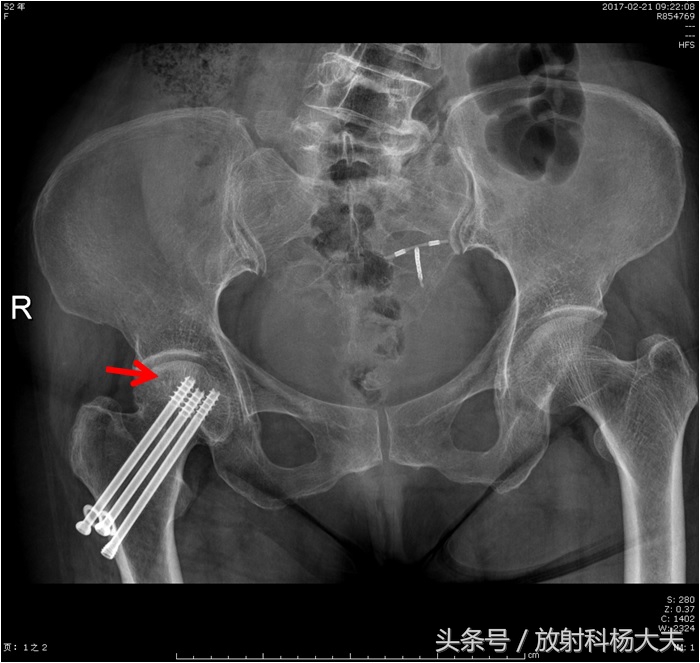

保守治疗,约一年后复查,这次又拍了X光片。